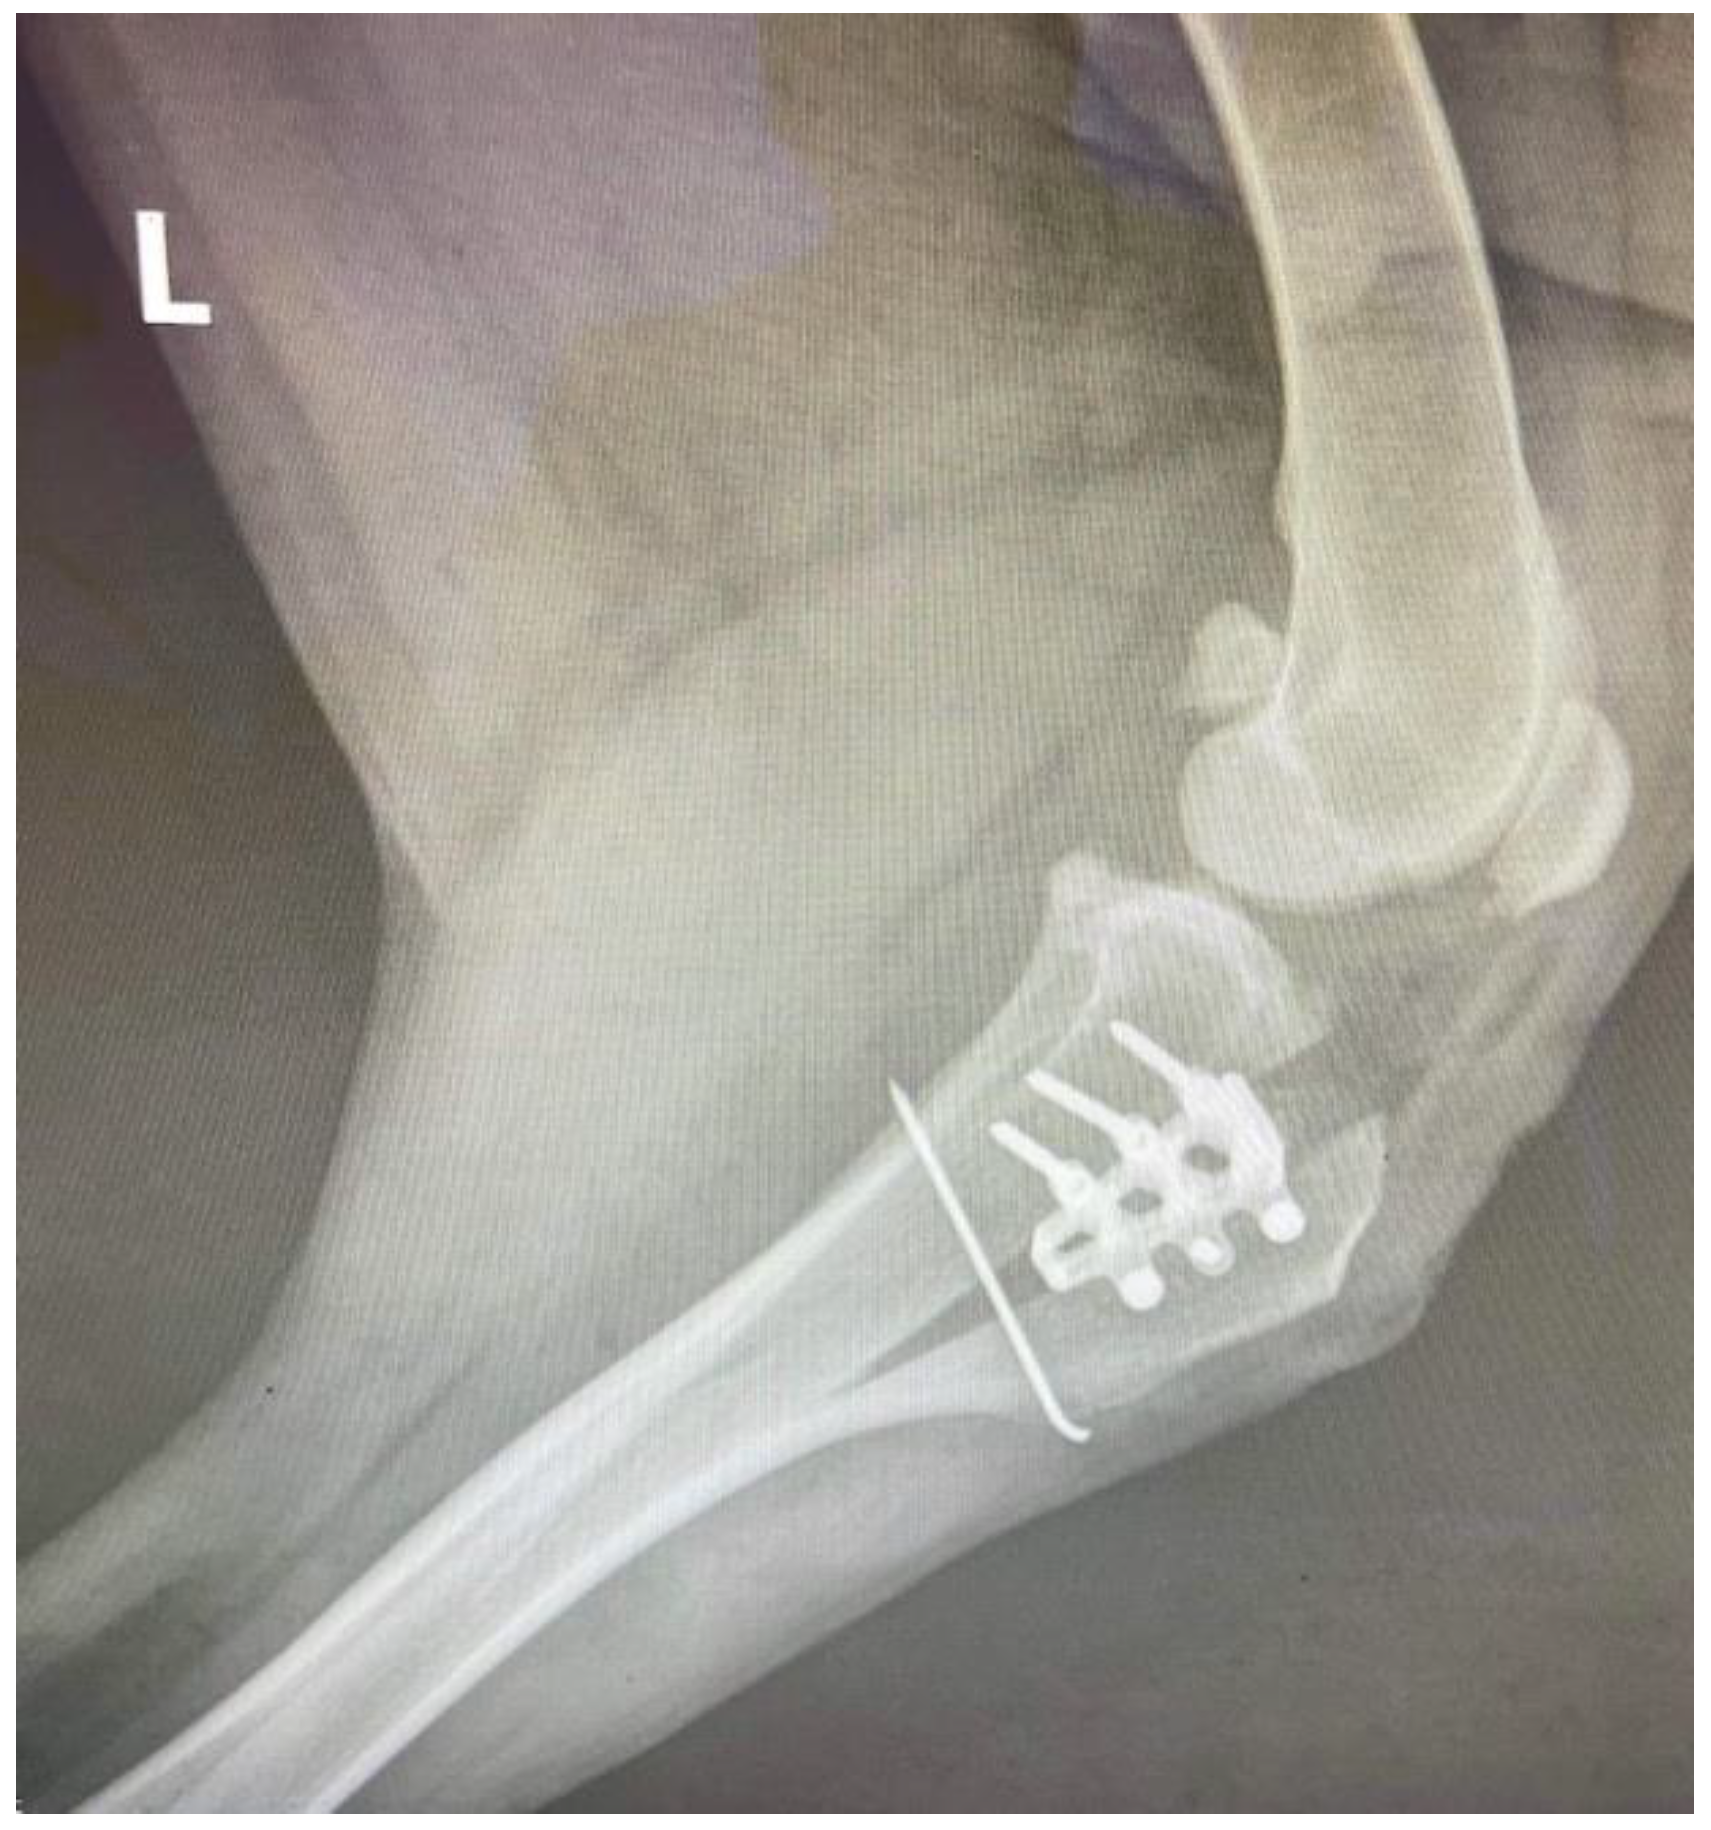

Modified Tibial Tuberosity Advancement Rapid in a Dog with One Contralateral Amputated Limb

2. Detailed Case Description